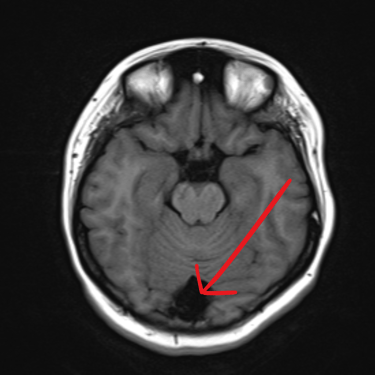

El quiste aracnoideo suboccipital es una lesión benigna de origen congénito, formada por una acumulación de líquido cefalorraquídeo entre las membranas aracnoideas. Aunque en muchos casos puede ser asintomático y detectarse de manera incidental, también puede producir cefalea, mareos, alteraciones del equilibrio o compresión del cerebelo y tronco encefálico. La resonancia magnética (RMN) es el estudio de elección, ya que permite definir la localización, tamaño y sus efectos sobre estructuras adyacentes. Este diagnóstico es clave para establecer la conducta terapéutica, que puede variar entre seguimiento clínico-radiológico o tratamiento quirúrgico en casos sintomáticos o de crecimiento progresivo.